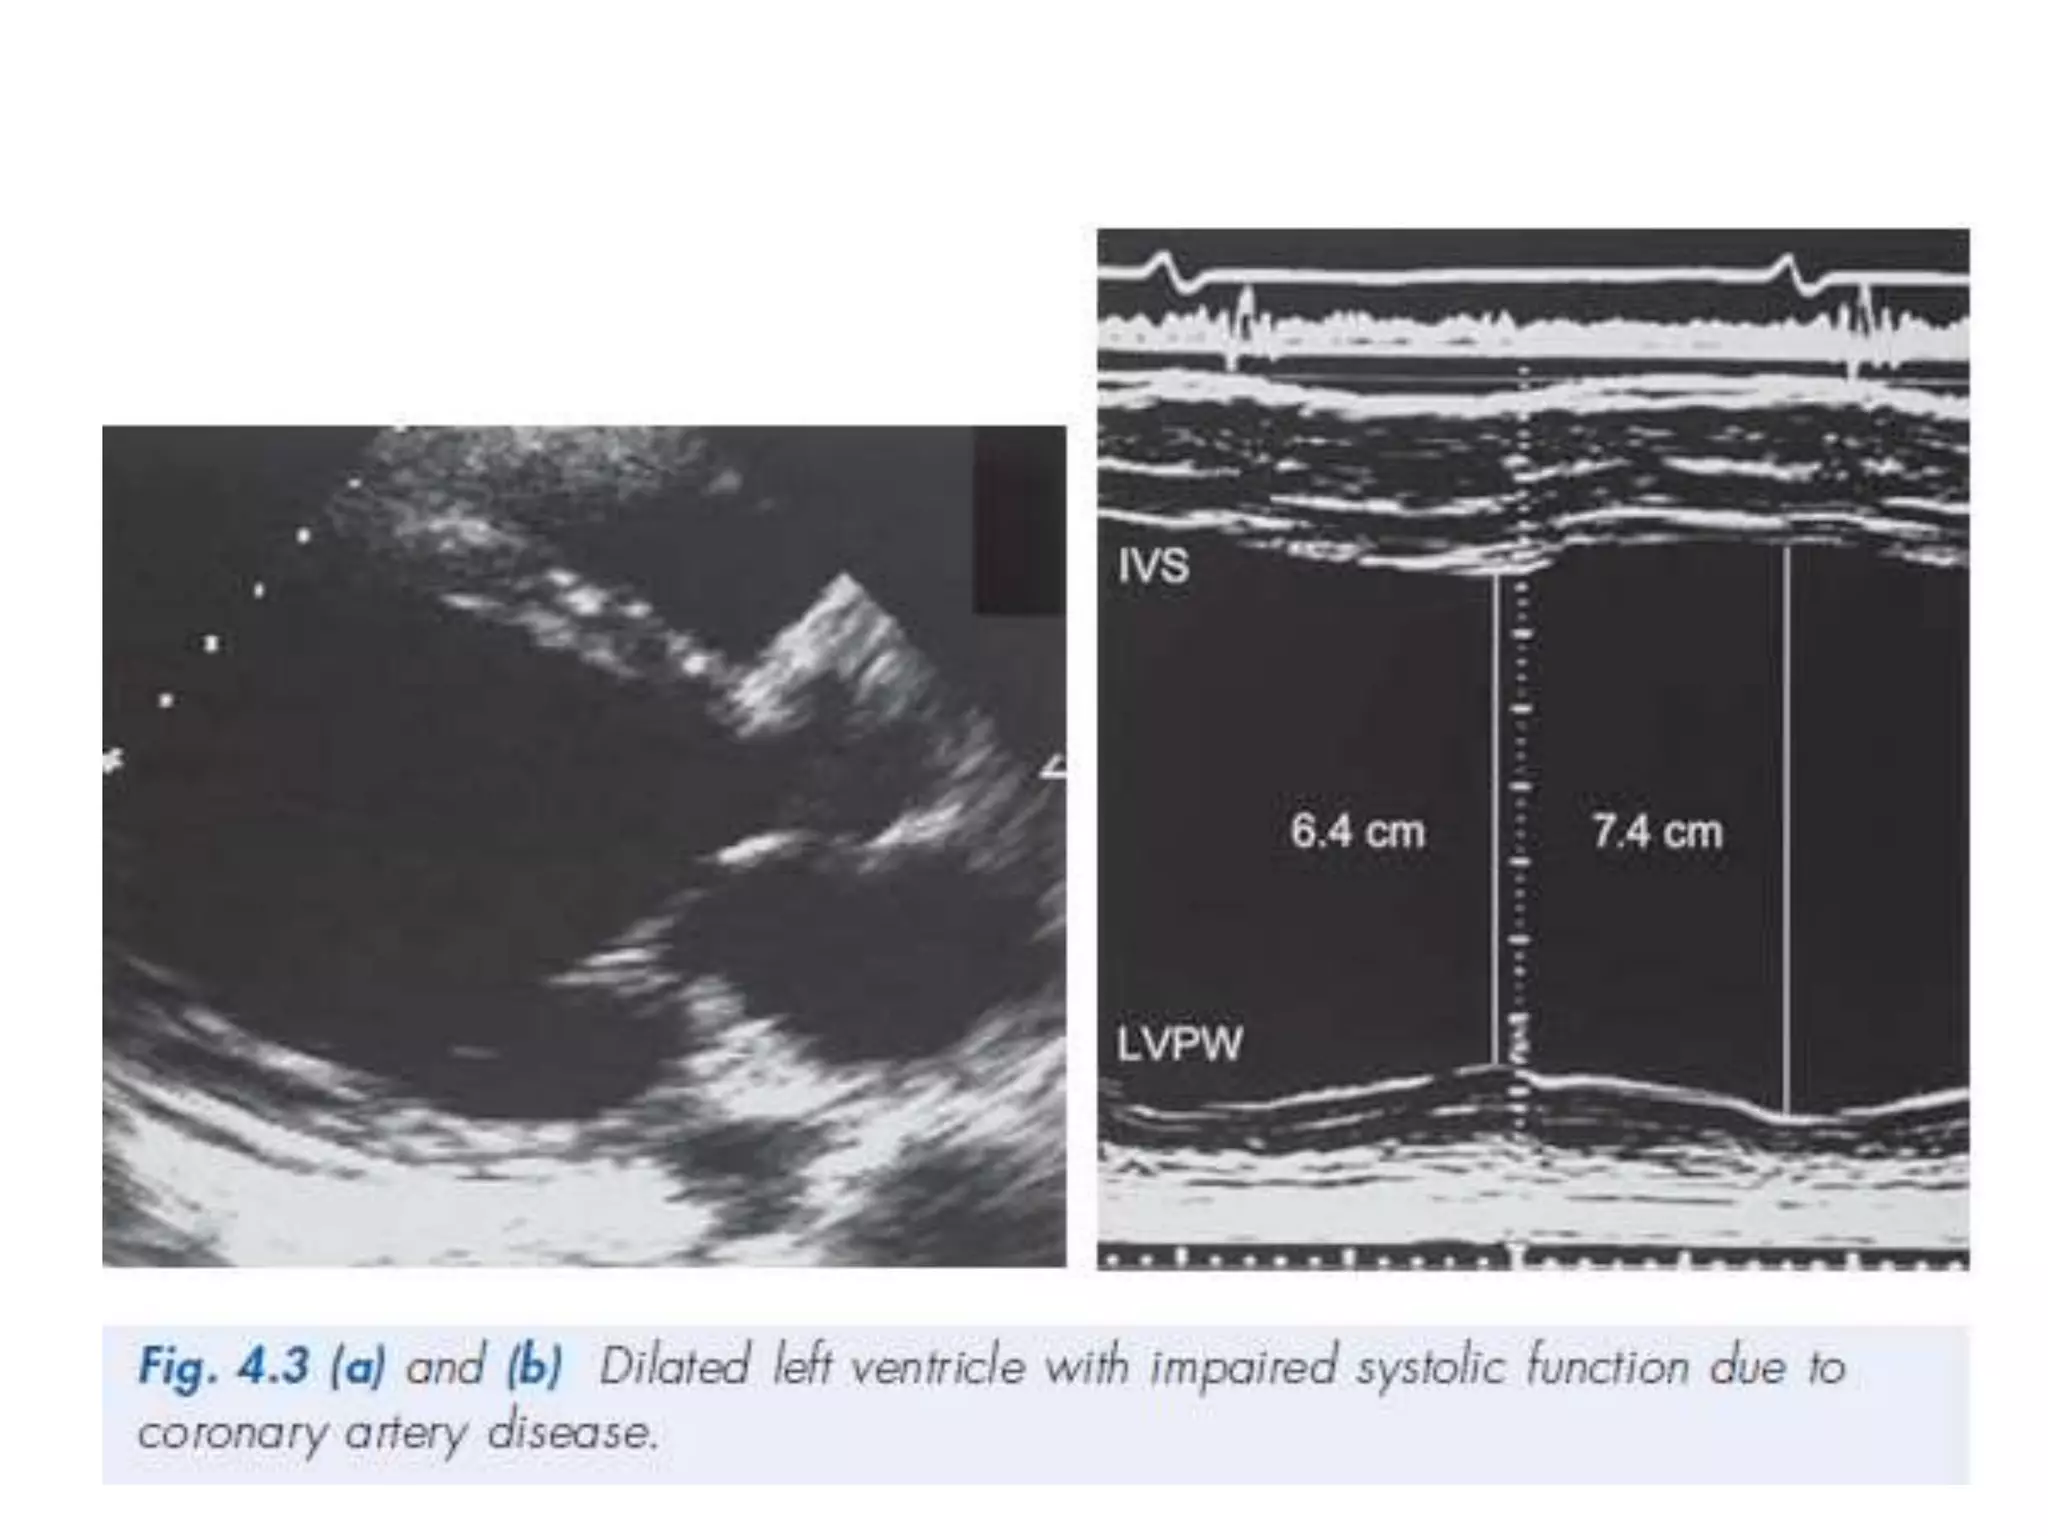

DCMP